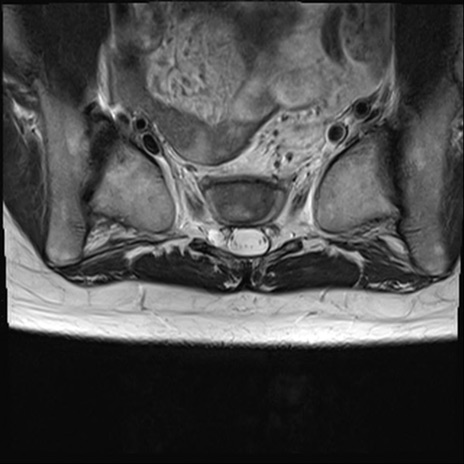

【整形】TIPS症例4 腰椎MRI T2WI(横断像)

腰椎MRI

横断像と矢状断像